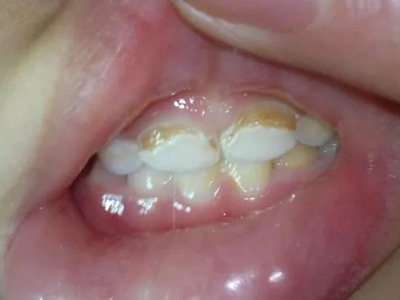

牙齿

坑

牙釉质发育不全牙表面上有坑图

牙釉质发育不全发展到严重时,导致牙釉质表面缺损,表现为带状、窝状的褐色凹坑,容易积存食物残渣诱发龋齿,表现为牙齿边上出现深褐色小洞。